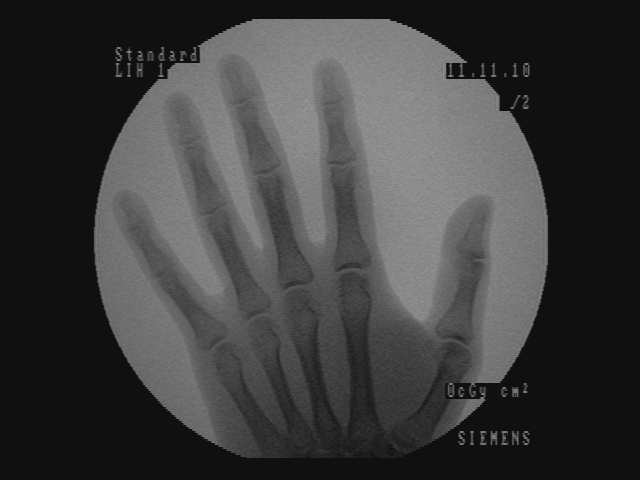

As a first step, the foreground needs to be segmented from the synthesized video image Icsubscript𝐼𝑐I_{c} and depth image Idsubscript𝐼𝑑I_{d}. A background model is computed from an initialization sequence of depth images where no hands or surgical instruments are introduced yet. An average depth image is created by averaging the depth at every pixel along the initialization sequence. Then, for every new image (with potential hands or surgical instruments present), the depth image Idsubscript𝐼𝑑I_{d} is compared to the mean image in order to create a binary mask image Imsubscript𝐼𝑚I_{m}. For every pixel whose depth is lower than the average depth minus a margin (3 cm), the pixel is classified as foreground and is set as white in Imsubscript𝐼𝑚I_{m}. If the pixel is classified as background, then it is set as black in Imsubscript𝐼𝑚I_{m}. The method is rudimentary compared to background subtraction methods, however the margin allows the background to change shape (in the limit of the margin). A noise removal step is added using morphological opening on the mask image. An example of scaled depth image and its corresponding mask are shown on Figure 3.

Refer to caption

Figure 3: The synthesized depth image and its corresponding segmented mask